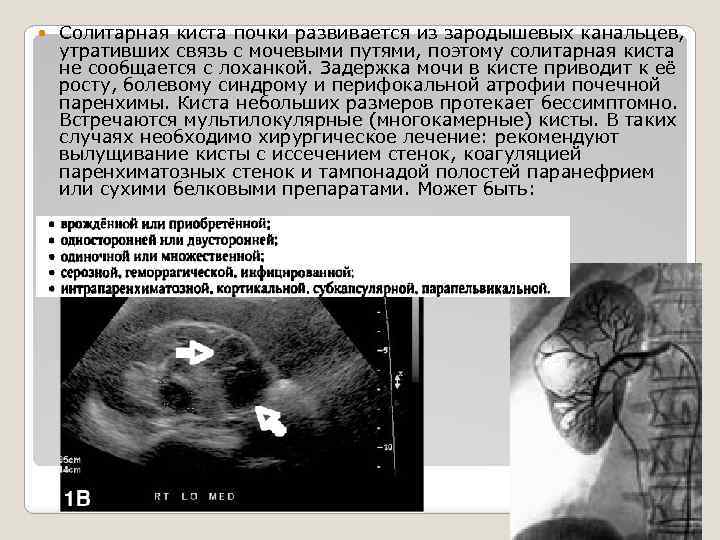

Солитарная киста почки развивается из зародышевых канальцев, утративших связь с мочевыми путями, поэтому солитарная киста не сообщается с лоханкой. Задержка мочи в кисте приводит к её росту, болевому синдрому и перифокальной атрофии почечной паренхимы. Киста небольших размеров протекает бессимптомно. Встречаются мультилокулярные (многокамерные) кисты. В таких случаях необходимо хирургическое лечение: рекомендуют вылущивание кисты с иссечением стенок, коагуляцией паренхиматозных стенок и тампонадой полостей паранефрием или сухими белковыми препаратами. Может быть:

Солитарная киста почки развивается из зародышевых канальцев, утративших связь с мочевыми путями, поэтому солитарная киста не сообщается с лоханкой. Задержка мочи в кисте приводит к её росту, болевому синдрому и перифокальной атрофии почечной паренхимы. Киста небольших размеров протекает бессимптомно. Встречаются мультилокулярные (многокамерные) кисты. В таких случаях необходимо хирургическое лечение: рекомендуют вылущивание кисты с иссечением стенок, коагуляцией паренхиматозных стенок и тампонадой полостей паранефрием или сухими белковыми препаратами. Может быть: